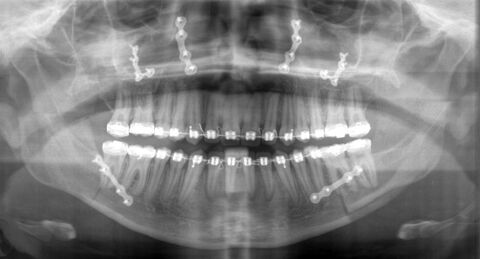

Kurz vor dem geplanten Operationstermin wird anhand von aktuellen Kieferabdrücken und Röntgenbildern Ihre individuelle Operation geplant und am Modell simuliert. Dies gibt Ihnen die größtmögliche Sicherheit, dass durch die folgende Operation die optimale Stellung der Kiefer erreicht wird. Dabei werden ebenfalls sogenannte Splinte, Kunststoffbissabdrücke, angefertigt, die dem Operateur wie nach dem Schlüssel-Schloss-Prinzip während der Operation die geplante Lage der Kiefer vorgeben. Zur Operation werden Sie bei uns stationär aufgenommen. Der Eingriff wird in Vollnarkose und ausschließlich über Schnitte innerhalb der Mundhöhle durgeführt. Das heißt für Sie, es werden äußerlich keine Narben zu sehen sein. Entsprechend der Modelloperation werden der Oberkiefer, der Unterkiefer oder wenn notwendig beide Kiefer innerhalb einer Operation verlagert. Dazu müssen der oder die Kiefer an bestimmten Stellen abgetrennt und in der festgelegten neuen Position wieder mittels kleiner Titanplatten und Schrauben fixiert werden. Diese Plättchen sind so fein, dass eine größere Kieferbelastung in der ersten Zeit nach der Operation zu einer Verschiebung der Kieferanteile führen kann. Deshalb werden Sie vorerst eine flüssige Diät einhalten müssen. Weiterhin wird für eine zügige Heilung eine Ruhigstellung der Kiefer, wie bei einem gebrochenen Bein, nötig sein. Dazu werden für kurze Zeit Ober- und Unterkiefer mit kleinen Gummis aneinander fixiert. Während dieser Zeit tragen Sie noch einen der Operationssplinte. Somit kann sich Ihr Körper an die neue Kieferposition langsam gewöhnen. Die Entlassung erfolgt ca. nach sieben Tagen. Im weiteren Verlauf werden Sie ambulant, anfangs engmaschig, in der Dysgnathiesprechstunde durch uns weiter betreut.

Der Kieferorthopäde beginnt dann mit der Vorbehandlung. Dazu werden die Zahnbögen ausgeformt, dass heißt es werden die Zähne pro Kiefer mittels festsitzender Spange möglichst in eine Normalstellung gebracht. Da die knöcherne Fehlbildung noch nicht behandelt wurde, wird sich die Fehlbisslage durch diese Vorbehandlung etwas verschlechtern. Dieser Behandlungsschritt ist jedoch für ein optimales Endergebnis unentbehrlich und dauert je nach Ausgangslage circa ein halbes bis ein Jahr. Zum Ende dieser kieferorthopädischen Vorbereitung werden sie mit aktuellen Kiefermodellen in unserer Dysgnathiesprechstunde zur Verlaufskontrolle und Festlegung des Operationstermins wieder vorgestellt. Ebenso werden die weiteren Schritte besprochen und natürlich alle Ihre Fragen beantwortet.